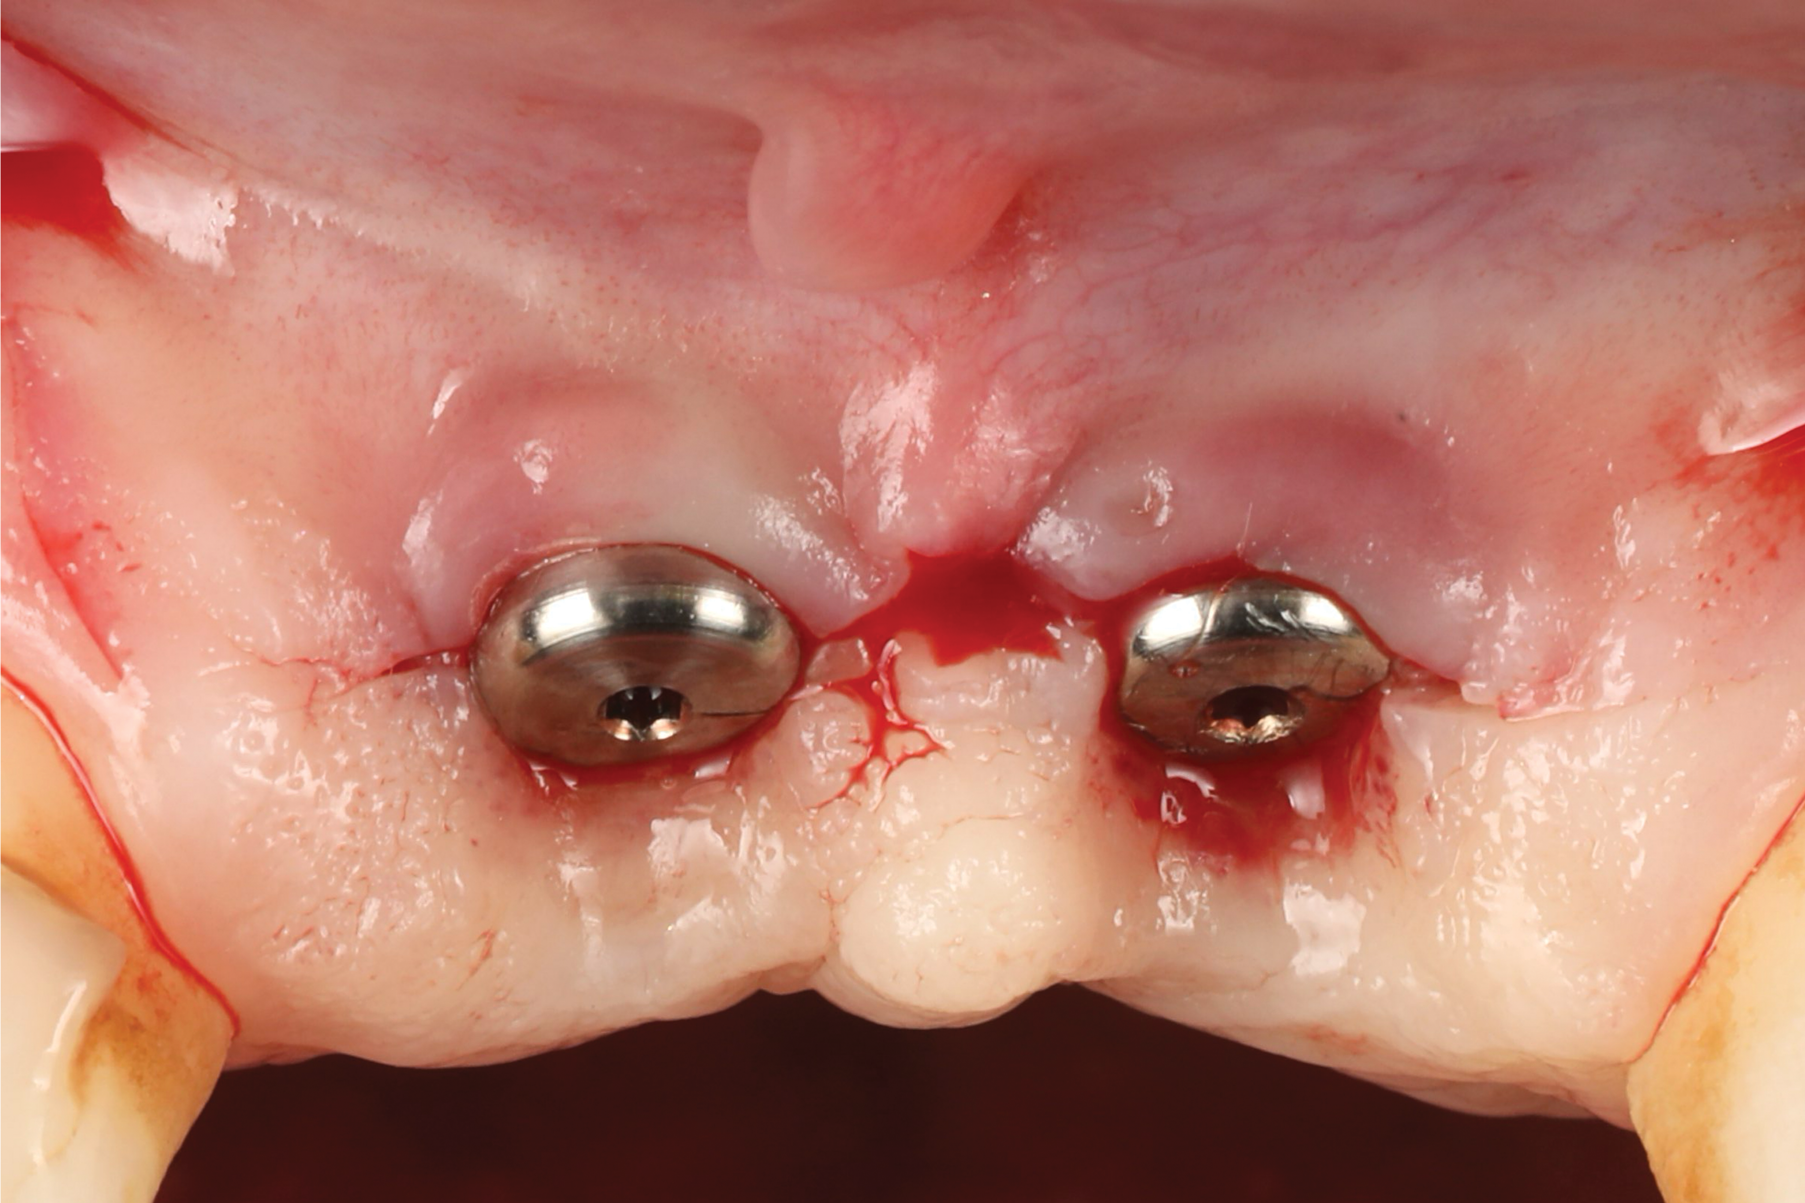

Oral hygiene instructions were reviewed with the patient and reinforced 6 weeks before the surgical visit. At the surgical appointment, the implant-supported crowns and abutments were removed, and two cover screws were inserted. A split-thickness trapezoidal-shape CAF was performed (Figure 3). The two slightly divergent beveled oblique incisions were placed between the implants and lateral incisors. A split-thickness flap was elevated, with meticulous care taken to maintain a layer of connective tissue adherent to the implant surface. Maintaining this layer of connective tissue on the implant body lacking buccal bone is an important step that differentiates flap elevation on healthy implants with PSTDs from implants with peri-implantitis (Figure 4).

Fig 4. Split-thickness flap elevation.

Figure 4

Fig 10. Flap elevation. Note that the mid portion of the flap was de-epithelialized to be rolled between the two implants.

Figure 10

Fig 11. Split-thickness flap elevation. Note the increased soft-tissue thickness on the buccal aspects of the implants.

Figure 11

Fig 17. Clinical comparison of the volumetric gain obtained with the intervention, occlusal views. Fig 17: Occlusal view at baseline. Fig 18: Occlusal view at 1-year post-treatment.

Figure 17

Fig 18. Clinical comparison of the volumetric gain obtained with the intervention, occlusal views. Fig 17: Occlusal view at baseline. Fig 18: Occlusal view at 1-year post-treatment.

Figure 18